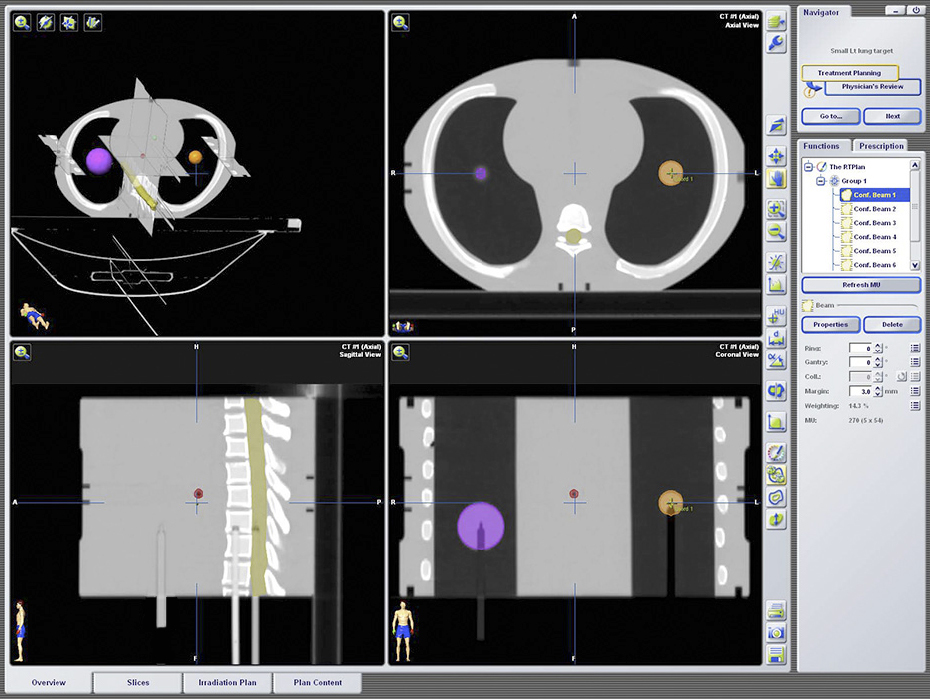

The End-to-End SBRT Phantom is a single tool for high-accuracy end-to-end commissioning and routine QA necessary for the high dose per fraction associated with SBRT deliveries.

Daily System Checks

The E2E SBRT Phantom contains multiple targets and alignment marks for verifying that imaging, localization, and targeting systems are aligned. This is a critical need for accurate delivery of these high-dose treatments.